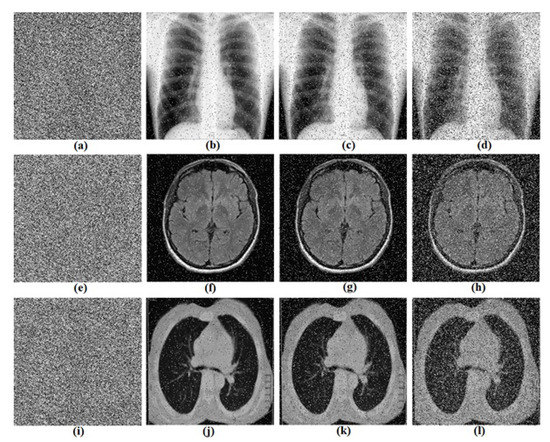

5. Biomedical Images Encryption Based on RNG Obtained from the Oscillator

5.1. Proposed Biomedical Images Encryption Algorithm

5.2. Computational Results